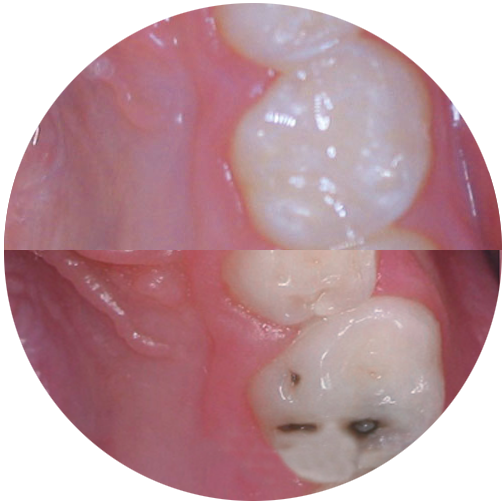

Wir machen ausschließlich weiße Füllungen. Dabei kann es sich um Komposite, Kompomere oder Glasionomerzemente handeln. Welches Material wo zum Einsatz kommt hängt von vielen Faktoren ab, die wir individuell mit Ihnen besprechen.

Bei Kompositen handelt es sich um hochwertige Kunststoffe, wie sie in der Erwachsenenbehandlung ebenfalls verwendet werden. Diese verwenden wir selbstverständlich bei allen bleibenden Zähnen sowie bei Milchzähnen, wenn er noch viele Jahre halten muss.